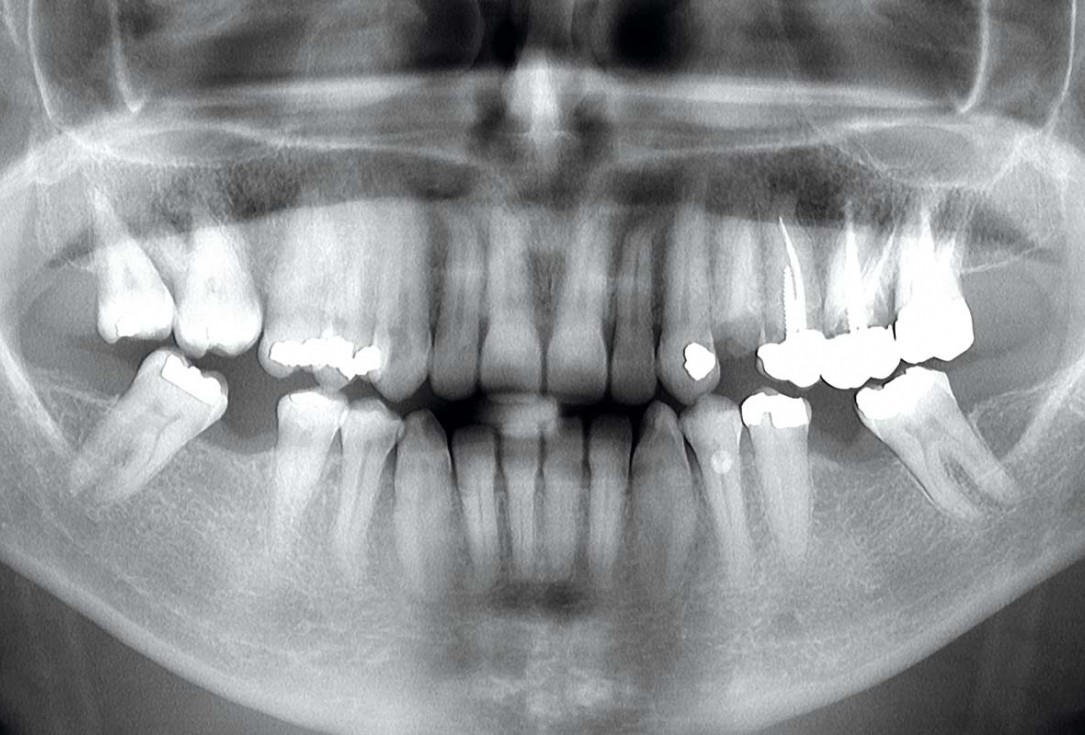

1/13 - Pre-operative OPG, teeth 24, 25, and 26 planned for extraction

Multiple socket preservation in the maxilla with collacone® max – Dr. D. Jelušić